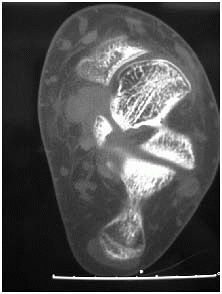

the calcaneus to help make treatment decisions. The coronal views show

the important posterior facet and the sustenaculum tali and the height

and width of the heel. The position of the peroneal tendons and flexor

hallucis tendon can also be seen. The sagittal views provide additional

information about the posterior facet and also show the anterior

process well. The axial views visualize the calcaneocuboid joint well,

the anteriorinferior aspect of the posterior facet, and the

sustenaculum tali. This information can then be used in planning the

reconstruction of the calcaneus.144,145